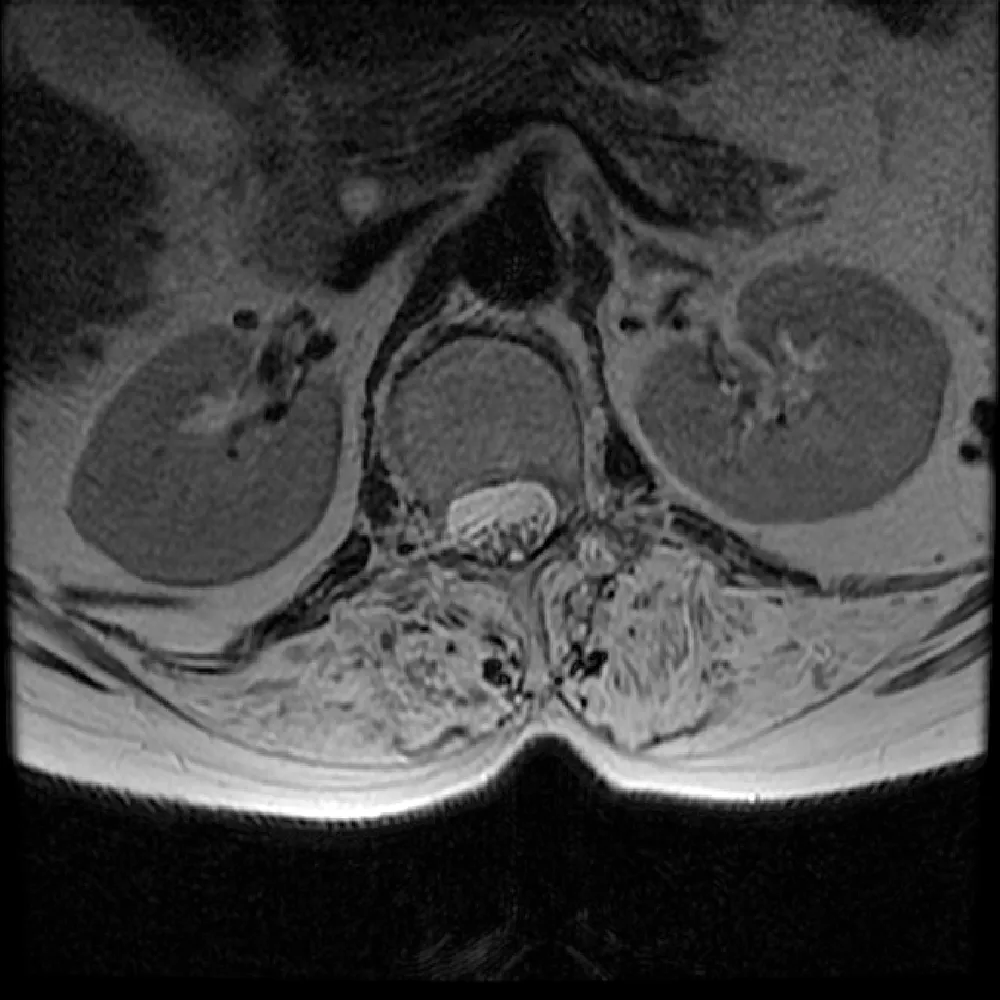

Typisch für unspezifische Rückenschmerzen ist, dass oft keine strukturellen Ursachen erkennbar sind. Diese Ungewissheit führt häufig zu einer Verunsicherung bei den Betroffenen. In der Hoffnung, eine Ursache zu finden, werden dann bildgebende Untersuchungen wie Magnetresonanztomografie (MRT) oder Röntgen durchgeführt, die dann häufig alters- oder verschleißbedingte Veränderungen zeigen. Diese radiologischen Befunde haben jedoch oft keinen realen Bezug zu den empfundenen Schmerzen.

Strukturelle Veränderungen an der Wirbelsäule sind auch bei einem erheblichen Anteil der beschwerdefreien Bevölkerung nachweisbar. So zeigen etwa 37 % der 20-Jährigen, die keine Rückenschmerzen haben, bereits degenerative Veränderungen im Bereich der Bandscheiben. Bei Personen über 40 steigt dieser Anteil deutlich an: Mehr als die Hälfte weist Anzeichen einer „Black Disc“ auf, bei den über 60-Jährigen sind es sogar über 85 % (Brinjikji et al., 2014). Solche Veränderungen gehören also zum normalen Alterungsprozess des Körpers.

Die Diskrepanz zwischen dem, was auf dem Bild zu sehen ist, und dem, was empfunden wird, ist groß – und hier liegt eine Herausforderung in der Kommunikation. Wird etwa ein MRT-Befund vom Patienten als dauerhafte „Schädigung“ interpretiert, kann dies Ängste auslösen, das Vertrauen in die eigene Belastbarkeit untergraben und letztlich zu einer Reduktion körperlicher Aktivität führen.

Ein struktureller Aspekt, der bei der Beurteilung anhaltender Rückenschmerzen an Bedeutung gewinnt, ist die sogenannte Fettinfiltration der Rückenmuskulatur insbesondere im Bereich der Lendenwirbelsäule (L3–L5) (Abb. 1). Hierbei handelt es sich nicht um ein direktes Verschleißphänomen, sondern um die Einlagerung von Fettgewebe innerhalb der Muskulatur. Sie lässt sich mittels MRT sichtbar machen und wird als Marker für muskuläre Inaktivität interpretiert. Die intramuskuläre Verfettung tritt häufiger bei Menschen mit anhaltenden Rückenbeschwerden auf und gilt als Hinweis auf eine verminderte funktionelle Kapazität der stabilisierenden Rumpfmuskulatur. Der erhöhte Fettanteil kann die Kontraktionsfähigkeit einschränken, die neuromuskuläre Kontrolle und die Funktion der Wirbelsäule beeinträchtigen. Er lässt sich nicht allein durch eine allgemeine Gewichtsreduktion beeinflussen; auch Ausdauertraining hat nur einen begrenzten Effekt. Wirksamer ist der gezielte Aufbau funktioneller Muskelmasse insbesondere durch spezifisches Krafttraining der Rumpfmuskulatur. Gezieltes freies Krafttraining über einen Zeitraum von mehreren Wochen unter Einbezug funktioneller Grundübungen wie Kniebeugen kann nachweislich zu einer Reduktion der Fettinfiltration in der Rückenmuskulatur beitragen. Gleichzeitig lassen sich so positive Effekte auf die Ausdauer sowie auf die funktionelle Leistungsfähigkeit der Muskulatur beobachten (Welch et al., 2015).